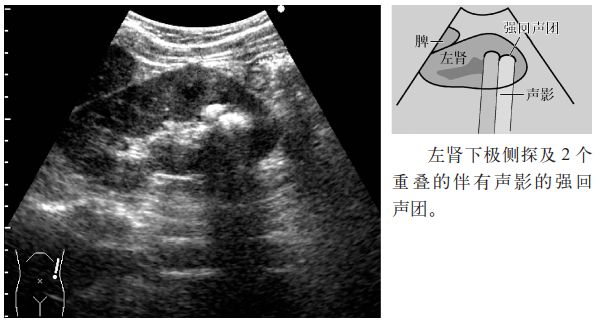

图1 肾结石

注意:小于5mm的肾结石几乎无声影,但是,超声入射角度微妙的变化可以显示点状高回声和声影。因此,平静呼吸时或改变经肋间扫查的位置,有时会出现声影,因此,不仅要在吸气时观察,还应在呼气时或改变经肋间扫查的位置时进行观察。